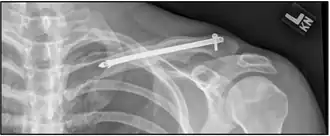

X-ray of the above comminuted fracture treated with an intramedullary fixation device

In children, breaks in the middle of the clavicle treated with surgery resulted in faster recoveries but more complications.[14] The evidence for different types of surgery for breaks of the middle part of the clavicle is poor as of 2015.[15]

A discontinuity in the bone shape often results from a clavicular fracture, visible through the skin, if not treated with surgery. Surgical procedures often call for open reduction internal [plate] fixation where an anatomically shaped titanium or steel plate is affixed along the superior aspect of the bone by several screws. In some cases, the plate is removed after healing due to discomfort, to avoid tissue aggravation, osteolysis or subacromial impingement. This is especially important with a special type of fixation plate called hook plate.[17] With anatomical plates plate removal is considered an elective procedure that is rarely necessary. An alternative to plate fixation is elastic TEN intramedullary nailing. These devices are implanted within the clavicle's canal to support the bone from the inside. Typical surgical complications are infection, loss of sensation distal the incision due to inadvertent injury of one or several supraclavicular nerves (most common when using a horizontal surgical incision)[18], and nonunion of the bone (failure of the bone to properly fuse together). Major nerve injury to the brachial plexus or vascular injury is extremely rare.[19]